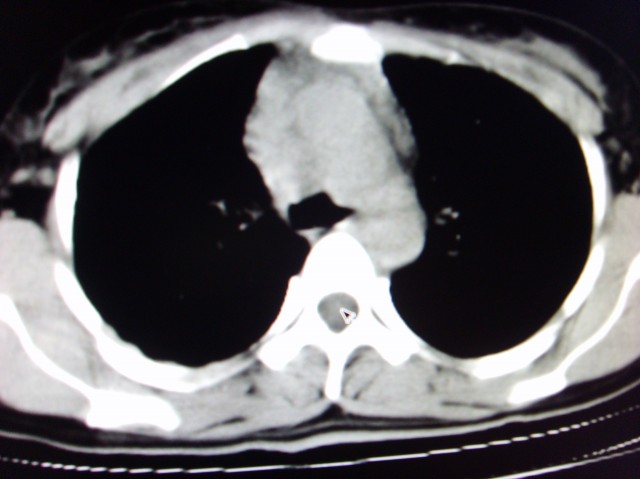

标题: CT7125:中央性肺Ca. [打印本页]

标题: CT7125:中央性肺Ca.

典型 中央型ca伴双肺、淋巴结转移

典型 中央型ca伴双肺、淋巴结、胸膜转移

右下中心型肺癌伴双肺转移、纵隔淋巴结转移,癌性淋巴管炎可能性大

中央型肺癌伴阻塞性肺炎

支持楼主的中央型肺癌,肺内,纵隔内淋巴结转移

典型的中央型ca伴双肺、纵隔淋巴结转移.

支持楼主诊断:中央型肺癌,肺内,纵隔内淋巴结转移。

典型--右下中心型肺癌伴双肺转移、纵隔淋巴结转移,癌性淋巴管炎可能性大

中心型肺癌伴双肺转移及纵隔淋巴结转移,癌性淋巴管炎

典型的中央型ca,肿快和肺门分界不清,肿快边界模糊,呈毛刺状。伴淋巴结转移。

首先考虑中央型肺癌伴阻塞性肺炎双肺、淋巴结转移,可以正规抗炎治疗一周后复查